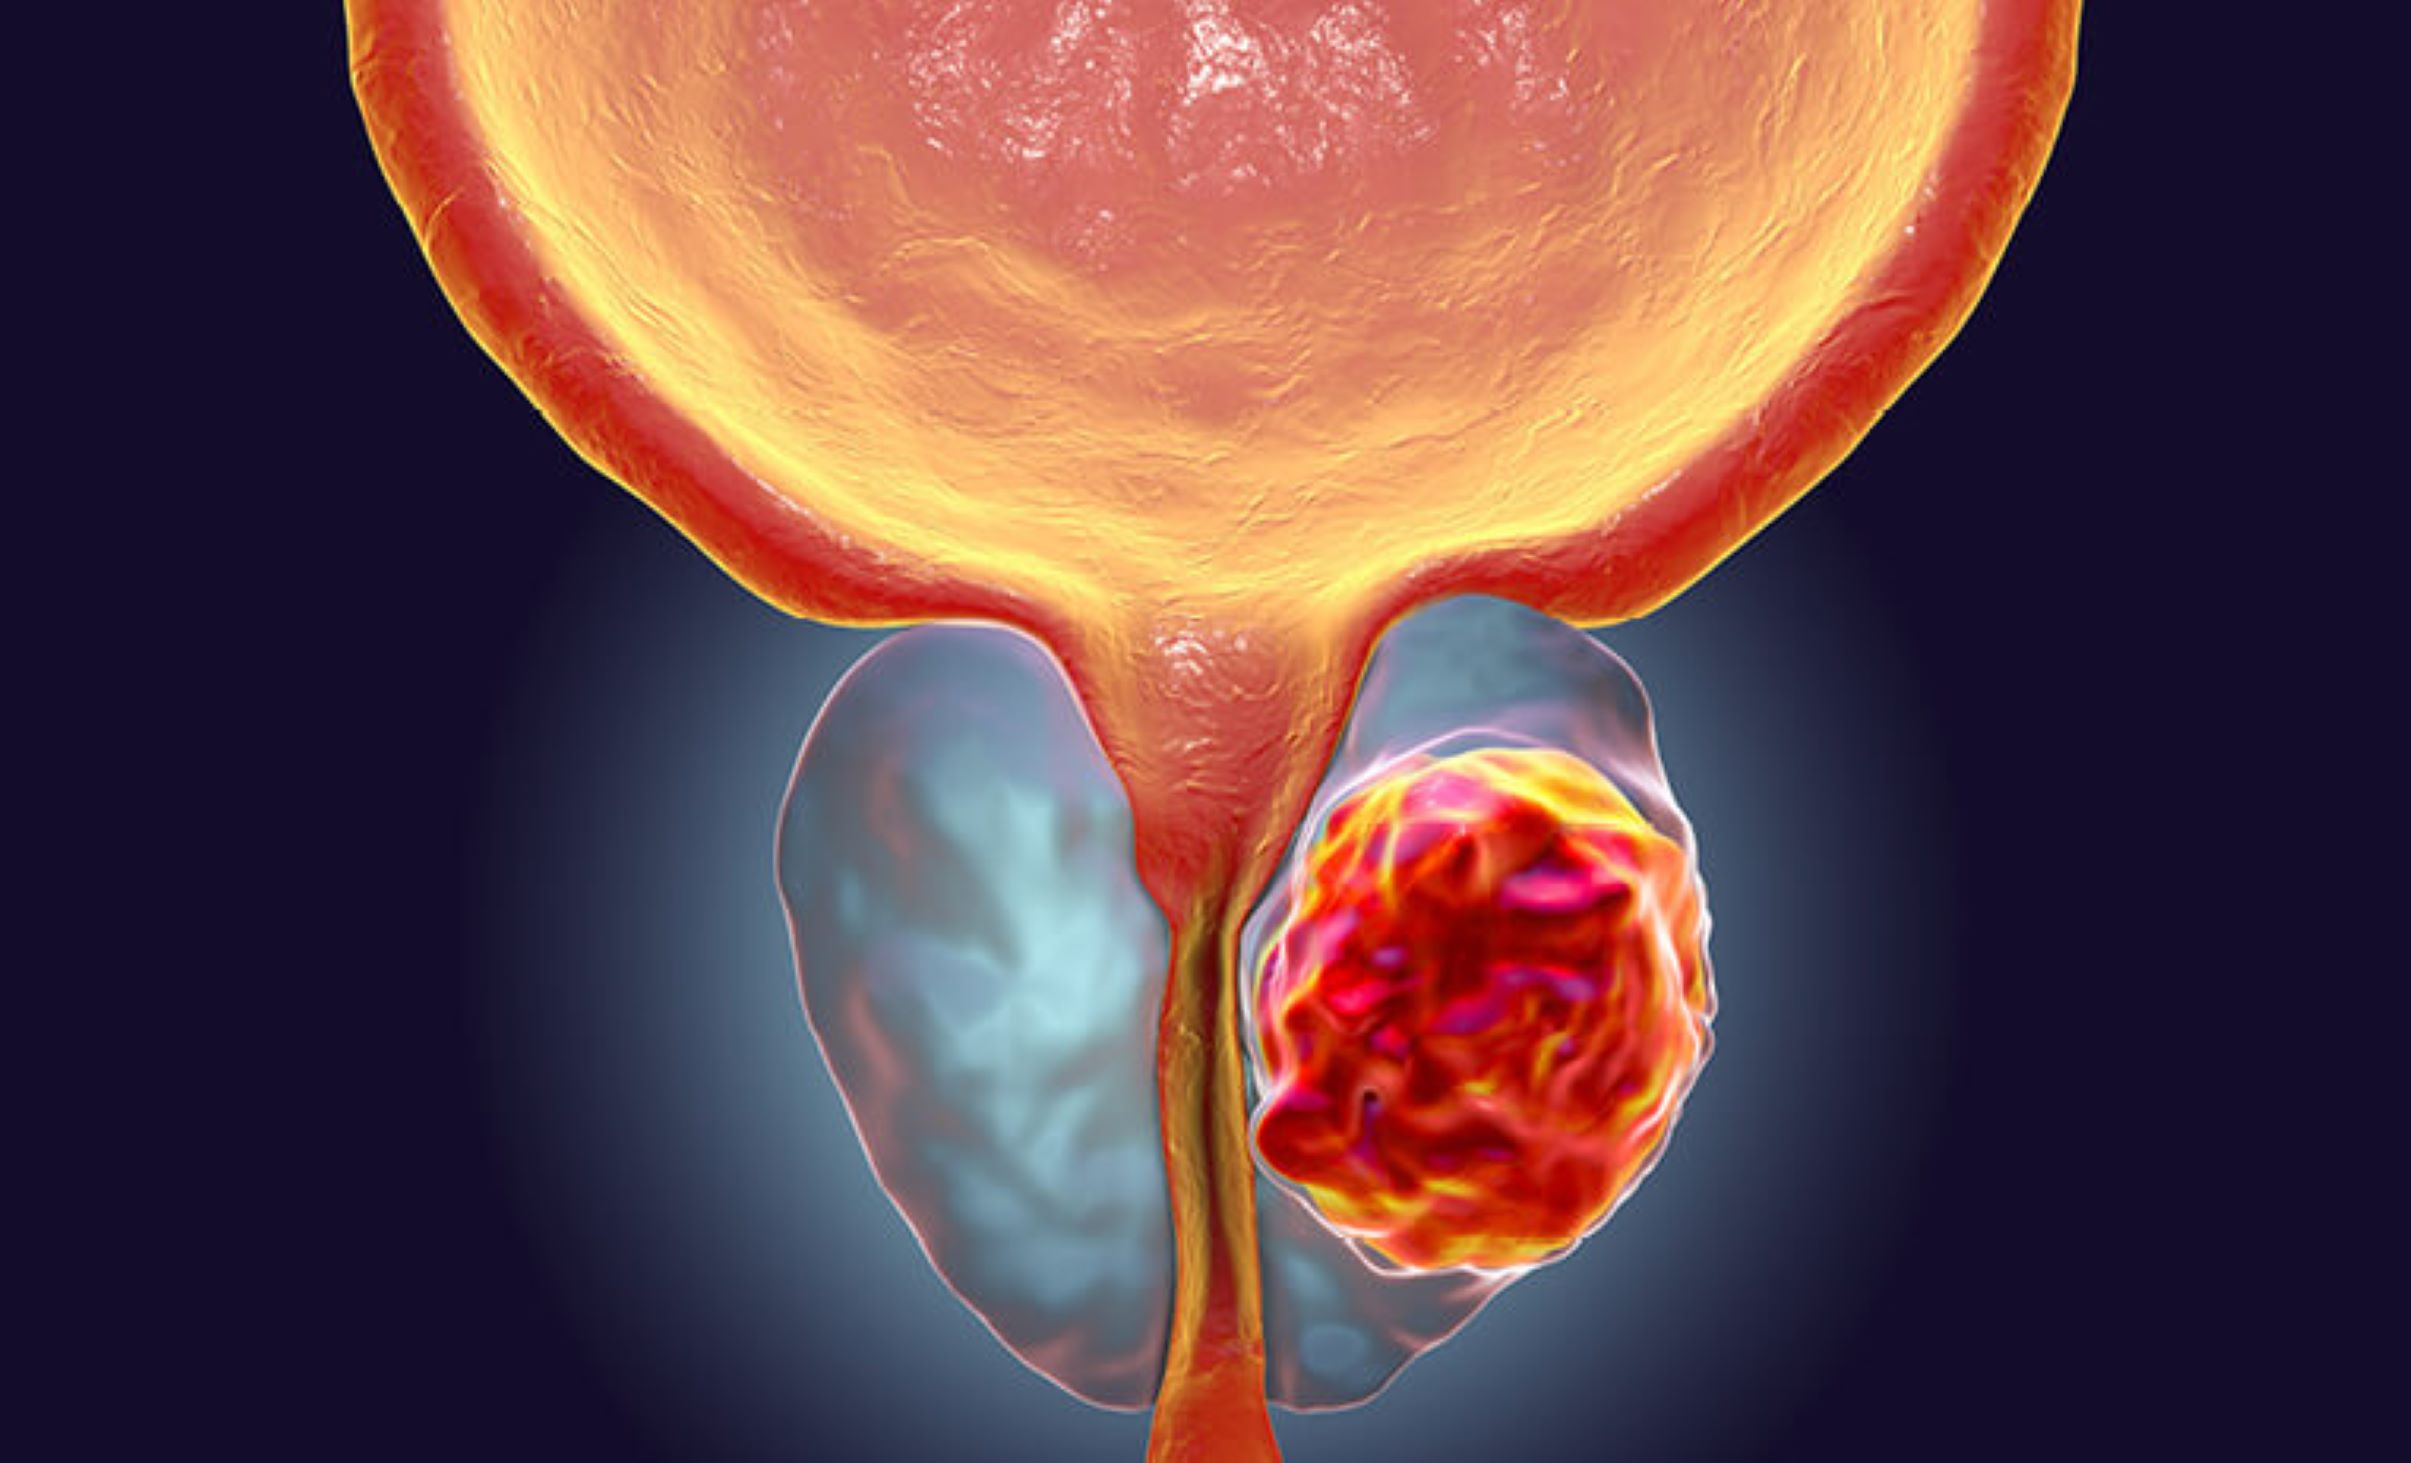

Ce magazine s’intéresse au cancer de la prostate. L’invité est Dr Albert Danaï, urologue-andrologue au Centre hospitalier universitaire de l’Amitié sino-centrafricaine.

Ce magazine s’intéresse au cancer de la prostate. L’invité est Dr Albert Danaï, urologue-andrologue au Centre hospitalier universitaire de l’Amitié sino-centrafricaine.